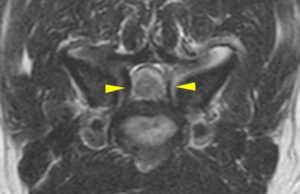

![[MR画像 背断像 T2強調画像]](https://saitovet.com/wp-content/uploads/2025/11/3-1-300x191.jpg)

![[MR画像 横断像(C5-6) T2強調画像]](https://saitovet.com/wp-content/uploads/2025/11/4-300x194.jpg)

この所見から脊椎の骨の増殖によって、脊髄が左右から圧迫される。

頚部脊椎脊髄症(ウォブラー症候群)と診断。